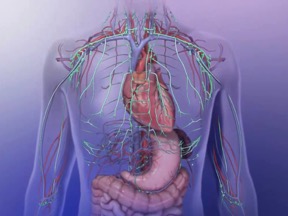

8. Sistem Limfatik

Mungkin ramai dikalangan perawat tradisonal dan komplimentari yang tidak sedar bahawa terdapat 2 jenis sistem rangkaian atau jaringan cecair pada tubuh. Selain sistem peredaran darah yang membincangkan rangkaian darah keseluruh tubuh, terdapat satu lagi peredaran cecair tubuh yang disebut cecair limfa atau ‘getah bening’ yang disebut sistem limfatik. Sistem ini adalah sebahagian dari sistem imuniti yang merangkumi jaringan sel, tisu dan organ yang bertanggung jawab dalam pengumbahan bahan-bahan toksin dan sisa-sisa metabolisma yang membentuk rangkaian pembuluh cecair limfa yang padat dengan sel darah putih sebagai agen pemusnah keseluruh tubuh. Pengetahuan dalam sistem tubuh ini pastinya dapat meningkatkan kefahaman akan ciri-ciri sistem imuniti tubuh yang sememangnya perlu diwarisi oleh setiap perawat perubatan.